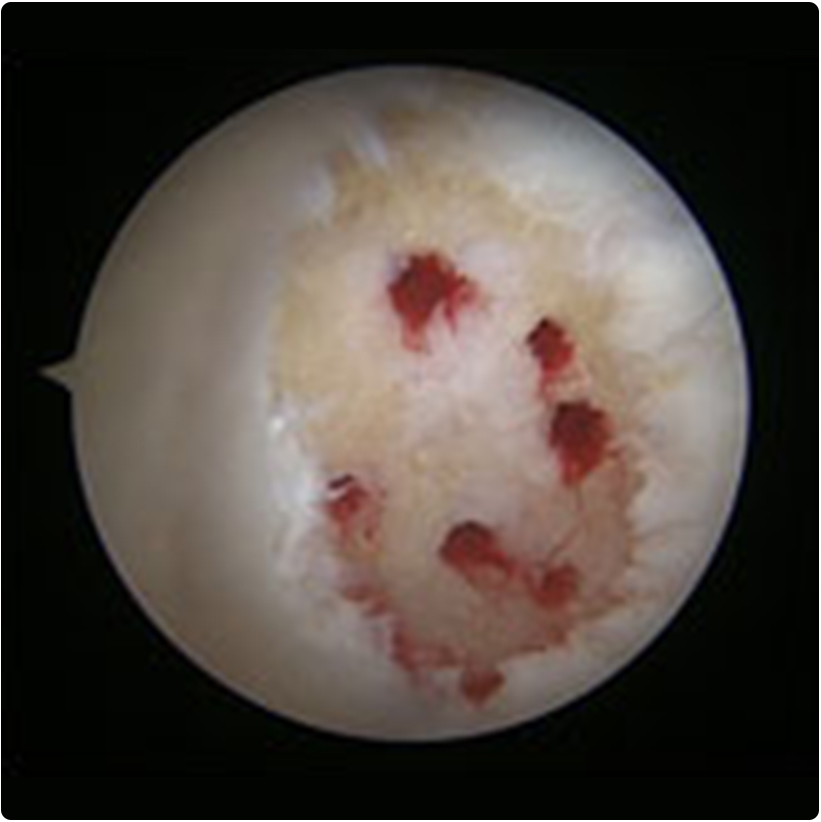

2- Mikrokırık yöntemi: yine artroskopik olarak yapılabilen bu yöntemde kıkırdaktaki hasarlı alanlar temizlenir ve kıkırdağın altındaki kemiğe özel

aletlerle delikler açılır. Böylece kemik iliğinden gelen kan, pıhtı ve birçok hücreye dönüşme yeteneğindeki kök hücreler hasarlı alanı doldurabilir. Bir süre sonra orijinal kıkırdak dokusu kadar güçlü olmasa da ona benzeyen bir dokuyla çukur doldurulmuş olur.  Bu girişim yük taşıyan bir alana uygulandı ise 4-6 hafta kadar yük vermeyi kısıtlayan bir fizyoterapi uygulanır.